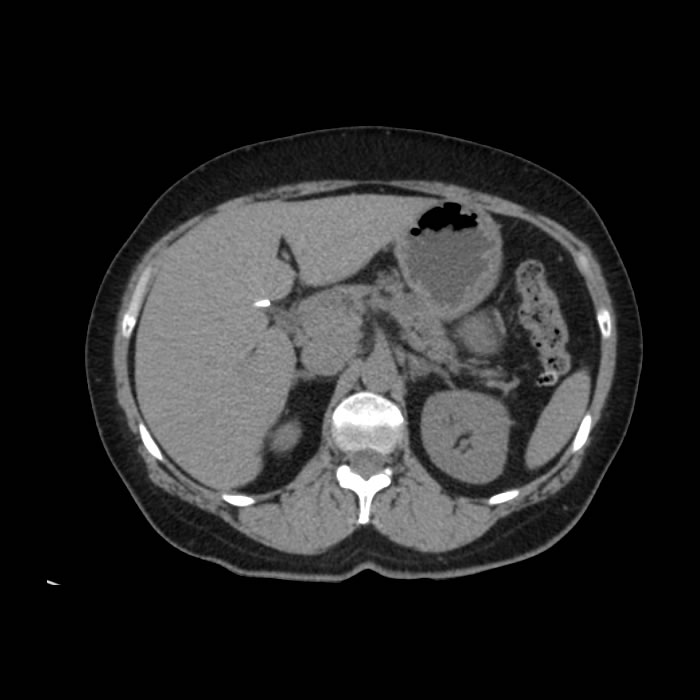

- Paciente de sexo femenino de 57 años de edad que acude a consulta por dolor abdominal irradiado hacia el flanco derecho. Al examen físico presenta abdomen blando con leve dolor a la palpación del marco colónico.

- Antecedentes de importancia: madre con antecedente de cáncer de colon.

- Antecedentes quirúrgicos: Colecistectomía, apendicectomía, cesáreas.